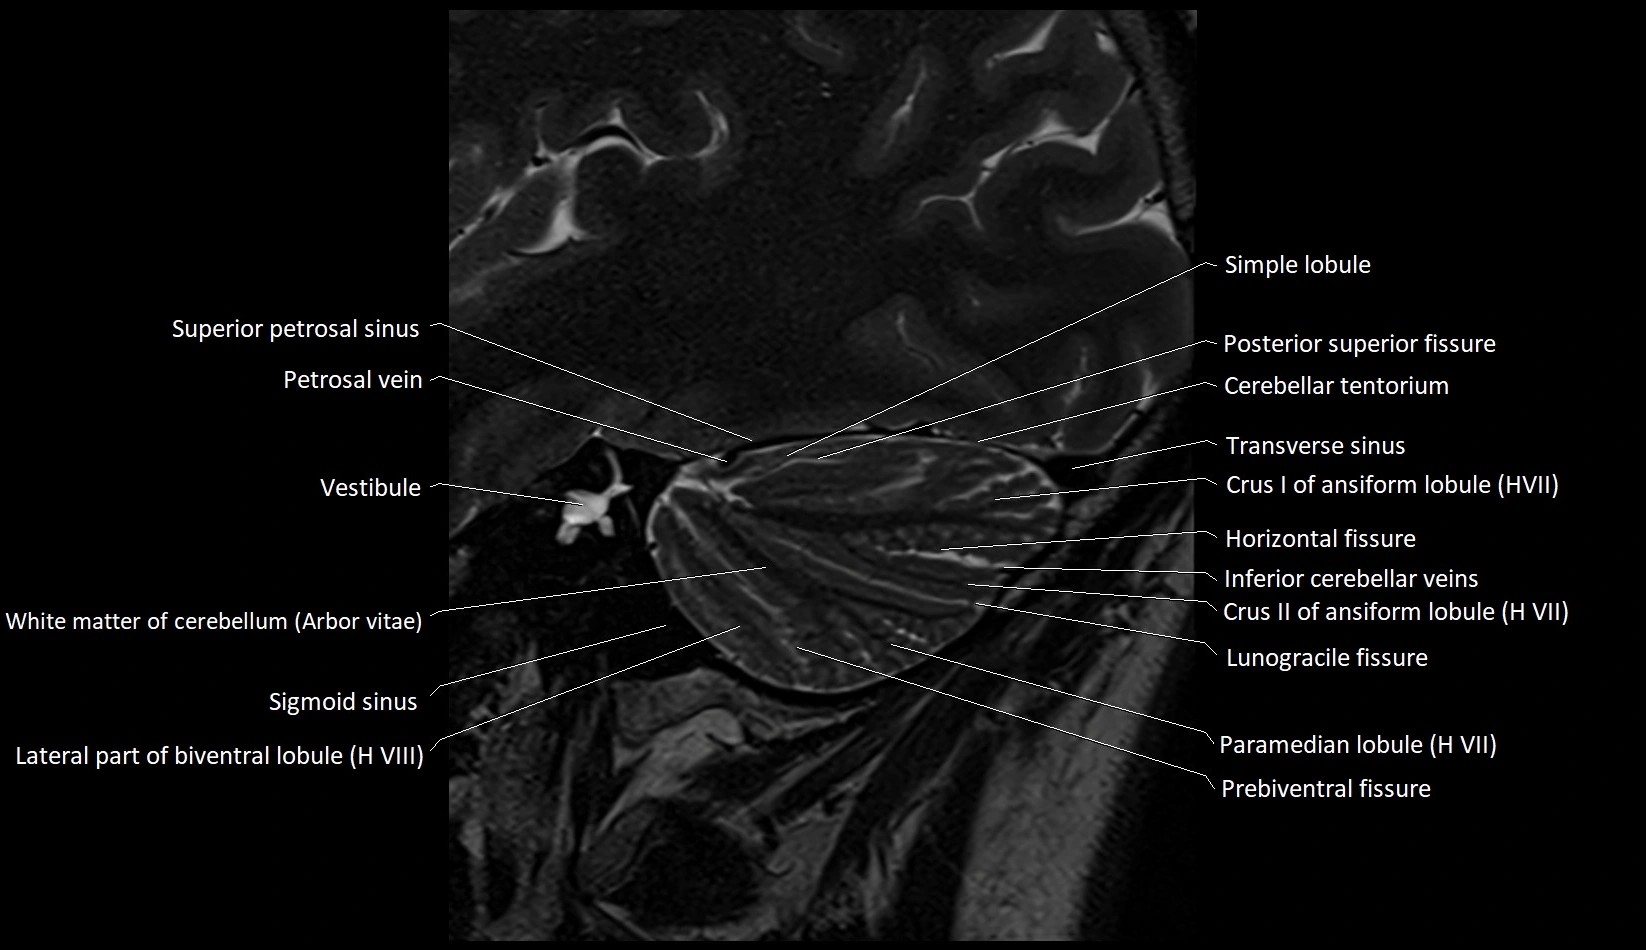

MRI images